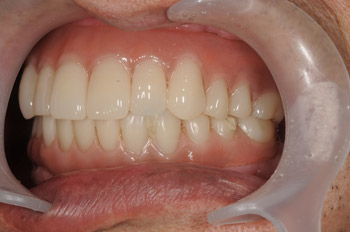

義歯に慣れずに食事が困難だった方の上下All-on-4

上下ALL-ON-4と骨造成による治療

歯周病で歯が抜けてしまい義歯を装着していましたが、義歯が合わずご飯も柔らかいものしか食べられないというお悩みで来院されました。

Before

歯周病で多くの歯を失い、残っている歯も延命は難しかったので、4本(上顎は6本)のインプラントですべての歯を並べるAll-on-4についてご説明させていただいき、All-on-4で治療を進めることを選択されました。

After

、All-on-4にて一日で手術が終わり、術後は患者様のお手入れのご協力もあり問題も起きず手術からおよそ3ヶ月で最後の歯がキレイに並びました。

今後も継続してメインテナンスに来ていただき、またご本人のセルフケアも継続して行っていただき、口腔内環境を保っていただけるよう担当医として努めていきます。

治療の内容 全顎オールオン4と骨造成による治療。

期間・回数 1年・14回(カウンセリング・検査含む)

費用 自由診療: 上下オールオン4+骨造成 総額 4,200,000円(税込 4,620,000円)